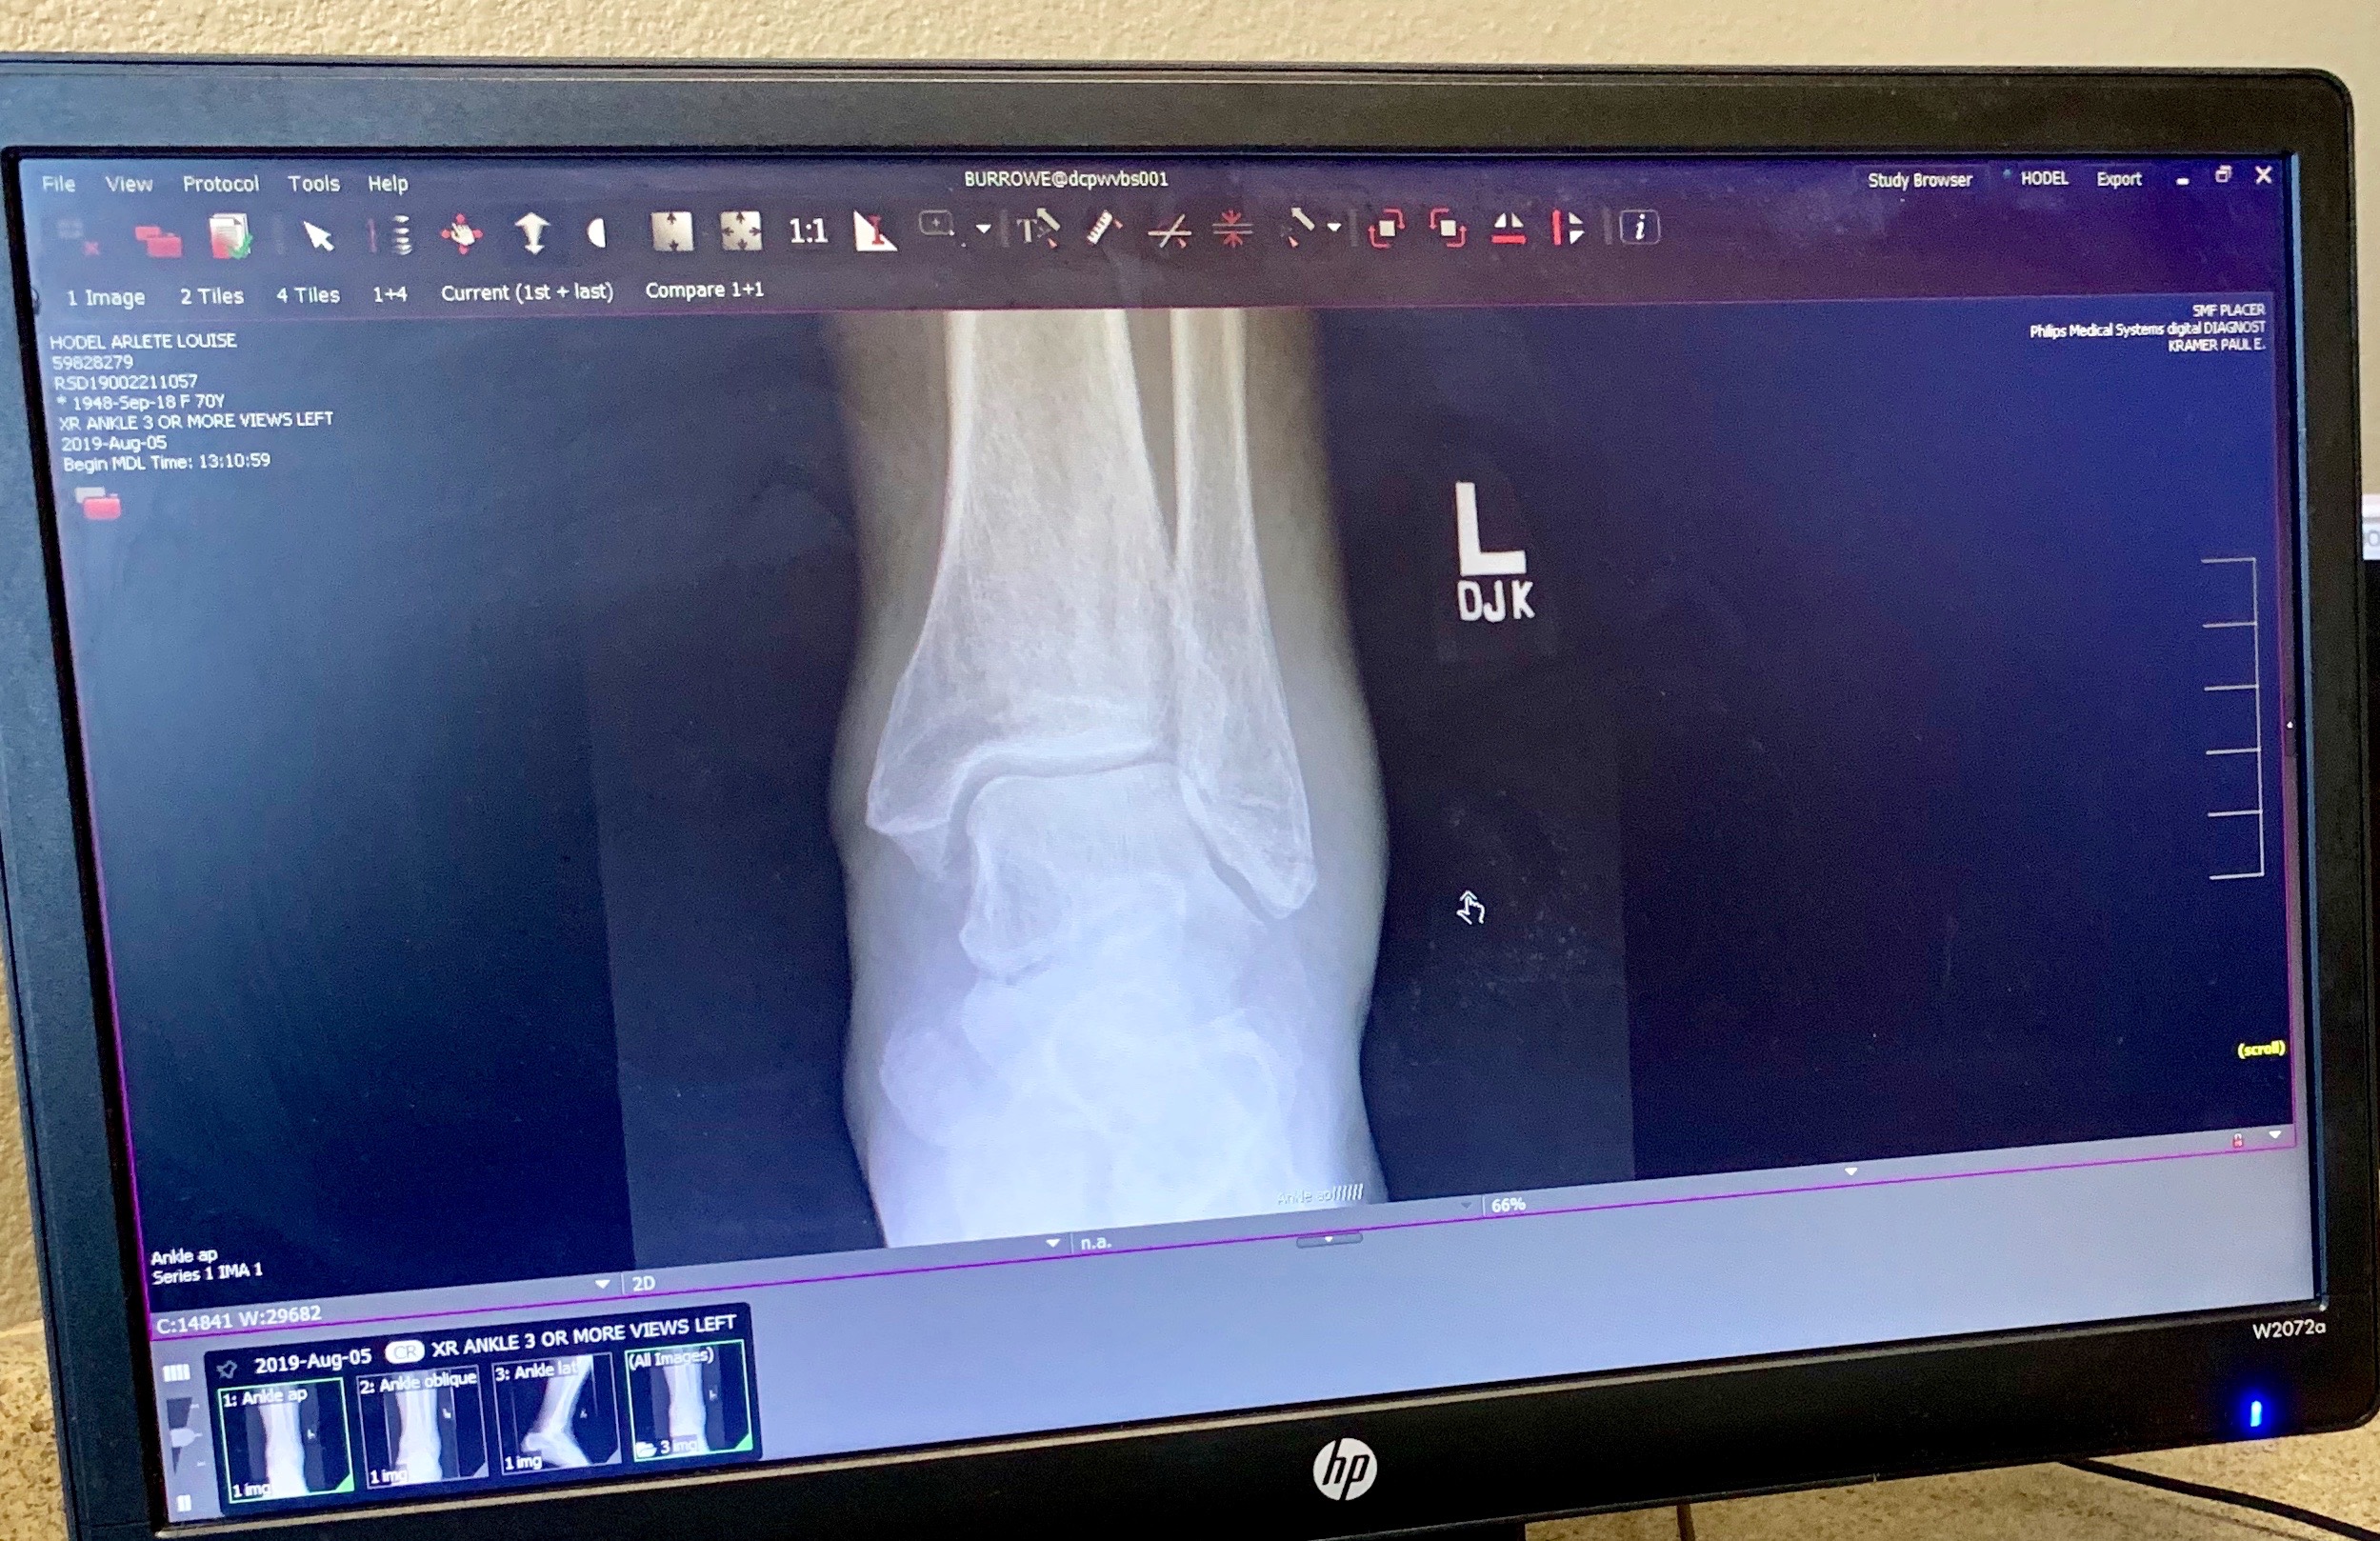

Monday morning. There’s a fairly big group of people here who play pickleball several times a week. I really like pickleball. In the second hour, we had a competitive doubles game going. I went for a shot, rolled my ankle, and fell. Pain! Everyone was great! Comforting words, do I need 911? (No), someone went for ice, another person went for a rolling chair, someone was holding my hand. Two people helped me into the rolling chair and into the shade. Everyone was so kind and helpful – I feel lucky to live in such a caring community! Lorraine rode my bike home and came back with crutches and her car. Waiting for Thais to take me to the doctor, but it doesn’t look good:

Broken ankle: week 1

Broken ankle: week 2

Broken ankle: week 3